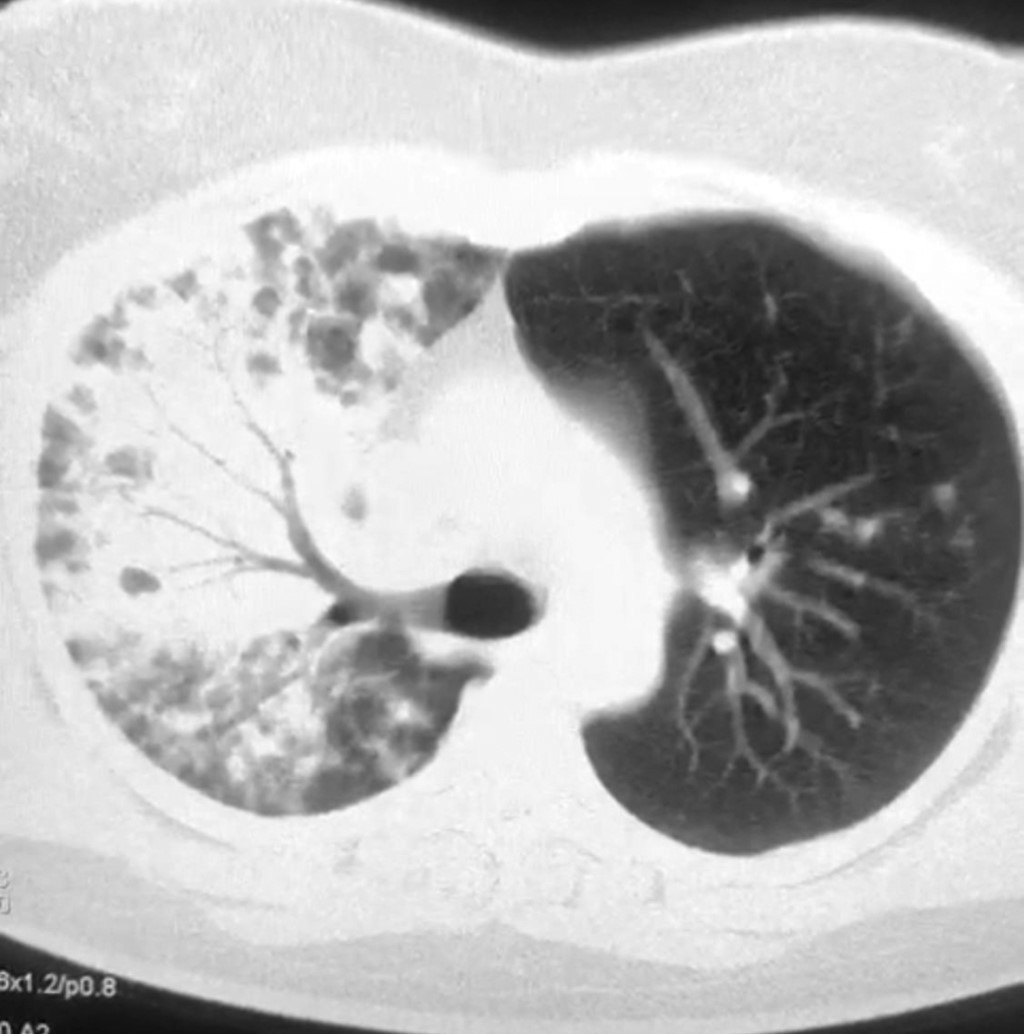

Inicia padecimiento en mayo de 2021 con rinorrea, astenia, adinamia, anosmia, disgeusia, tos, fiebre de 38 oC, dolor intermitente en hemitórax derecho de tipo pleurítico, disnea de medianos esfuerzos, motivo por el cual acude a médico particular, quien ante la sospecha solicita prueba de antígenos para COVID-19, la cual resulta positiva. Inicia tratamiento a base de esteroide y analgésico. Refiere discreta mejoría en las siguientes dos semanas; sin embargo, de manera súbita inicia con disnea de pequeños esfuerzos, por lo que acude al Servicio de Urgencias del Hospital General Tijuana, donde inicia con oxígeno suplementario con puntas nasales. En su abordaje se solicita radiografía de tórax, obteniendo parénquima con lesión radiopaca en región supradiafragmática externa derecha e hiliar externo derecho e izquierdo (Figura 1). Se realiza TAC de tórax, notándose lesión parahiliar derecha y broncograma aéreo de predominio apical e imagen en vidrio despulido en hemitórax izquierdo con un CO-RADS 3 (Figura 2). Además, se solicita hemograma en el cual se encuentran leucocitos de 28,420 a expensas de neutrófilos de 82.86%, iniciándose antibioticoterapia con levofloxacino.

Figura 2